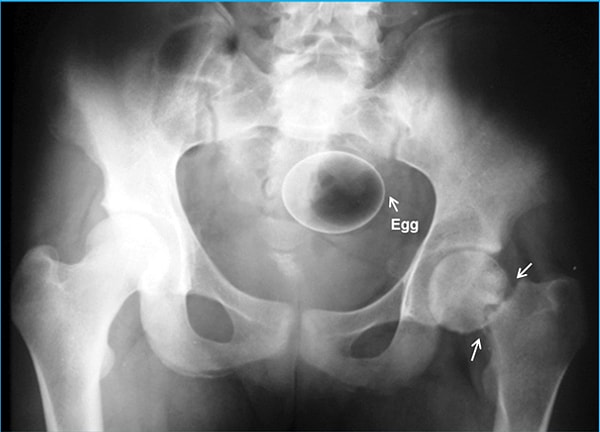

Итак, вашему вниманию предоставляются сами снимки. Попробуйте угадать, что там за предмет, если не сможете, то внизу есть подпись.

Баклажан.